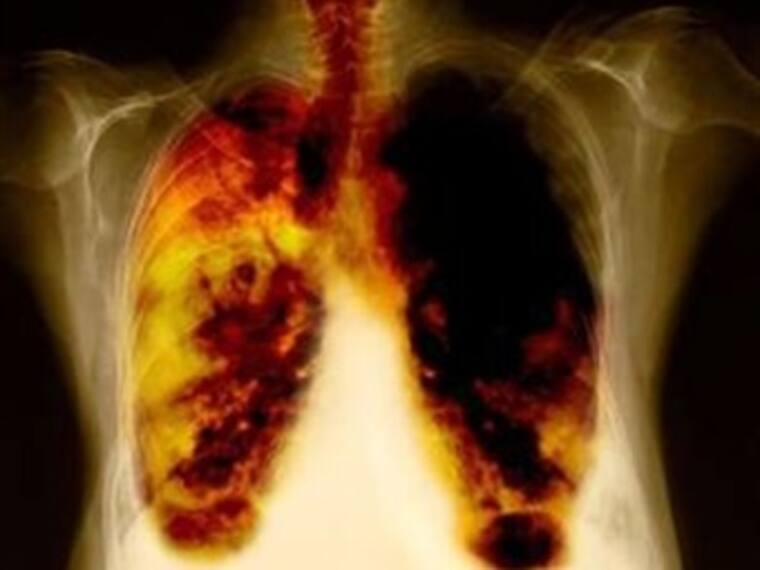

Gripes,influenza,otitis,sinusitis,faringitis,laringitis,bronquitis,neumonia,efisema pulmonar son las más comunes en esta época